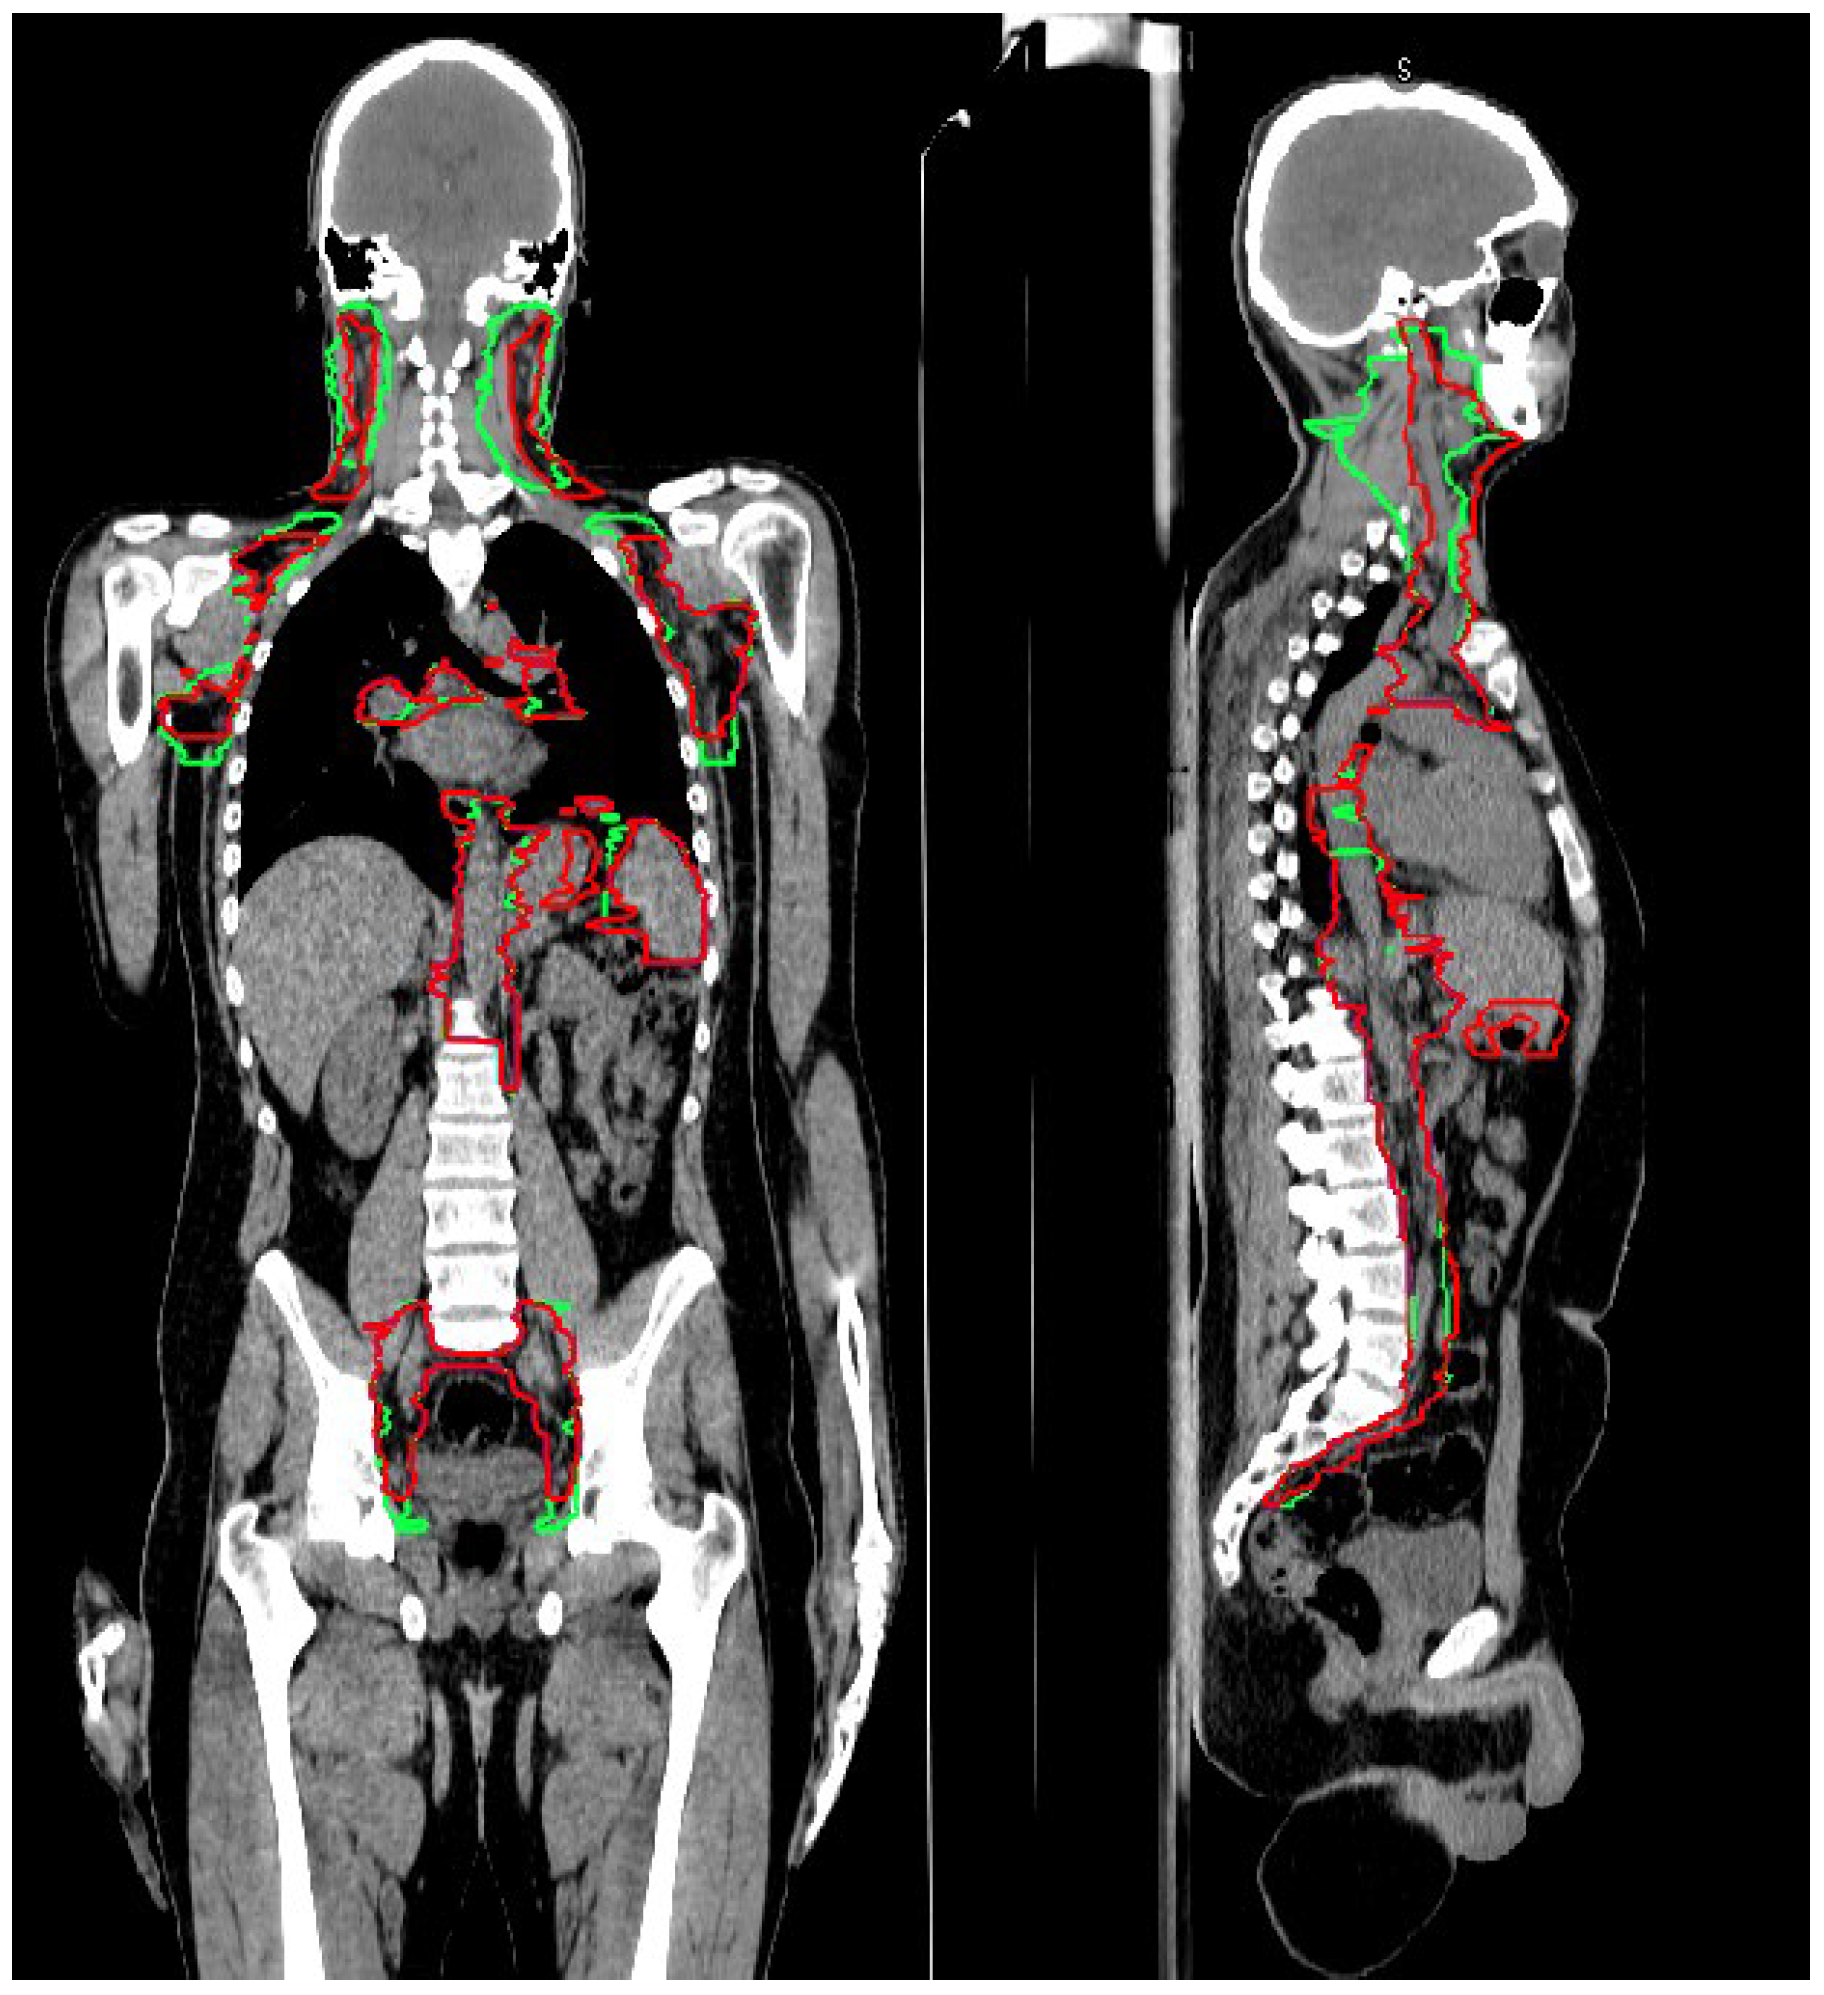

| CTV_LN Comparison | Comparison Abbreviation | Explanation |

|---|---|---|

| GL_RO1 vs. Old | A | After-GL vs. before-GL |

| GL_RO1 vs. GL_RO2 | B | Inter-observer-variability |

| GL_RO1a vs. GL_RO1b | C | Intra-observer-variability |

| LN levels | A | B | C | A vs. B | A vs. C | B vs. C | A | B | C | A | B | C |

| Tot | 0.82 ± 0.09 | 0.97 ± 0.01 | 0.98 ± 0.02 | 0.03 | <0.01 | 1.00 | 0.4 ± 0.2 | 0.1 ± 0.1 | 0.03 ± 0.02 | 7 ± 1 | 2 ± 2 | 1.9 ± 0.3 |

| H&N | 0.69 ± 0.15 | 0.88 ± 0.04 | 0.96 ± 0.03 | 0.27 | <0.01 | 0.13 | 0.5 ± 0.4 | 0.1 ± 0.1 | 0.02 ± 0.01 | 7 ± 7 | 2 ± 1 | 0.9 ± 0.3 |

| Thorax | 0.77 ± 0.15 | 0.97 ± 0.01 | 0.97 ± 0.02 | 0.18 | 0.02 | 1.00 | 0.5 ± 0.5 | 0.1 ± 0.2 | 0.03 ± 0.01 | 6 ± 7 | 2 ± 2 | 1.4 ± 0.5 |

| Abdomen | 0.82 ± 0.08 | 0.98 ± 0.01 | 0.97 ± 0.01 | 0.05 | 0.02 | 0.35 | 0.7 ± 0.4 | 0.1 ± 0.2 | 0.03 ± 0.01 | 8 ± 6 | 1 ± 2 | 1.6 ± 0.6 |

| Pelvis | 0.88 ± 0.09 | 0.96 ± 0.01 | 0.95 ± 0.03 | 0.27 | 0.16 | 0.80 | 0.2 ± 0.2 | 0.1 ± 0.2 | 0.06 ± 0.04 | 3 ± 2 | 1 ± 1 | 1.6 ± 0.5 |